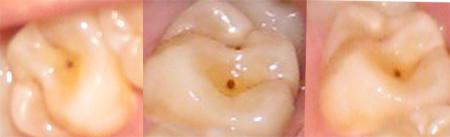

3、患有龋齿。有几种情况需要重视,比如虫牙,需要尽快处理,才能防止继续出现。

备孕前一定要补蛀牙吗

备孕前一定要补蛀牙吗?可能很多人都能理解到这个问题。但是对于备孕前来说,没有专门的牙齿,使用了相关药物可能会对孩子的牙齿造成很大的影响。所以备孕前一定要补蛀牙吗?我们看了下面的文章,一起来了解下吧。